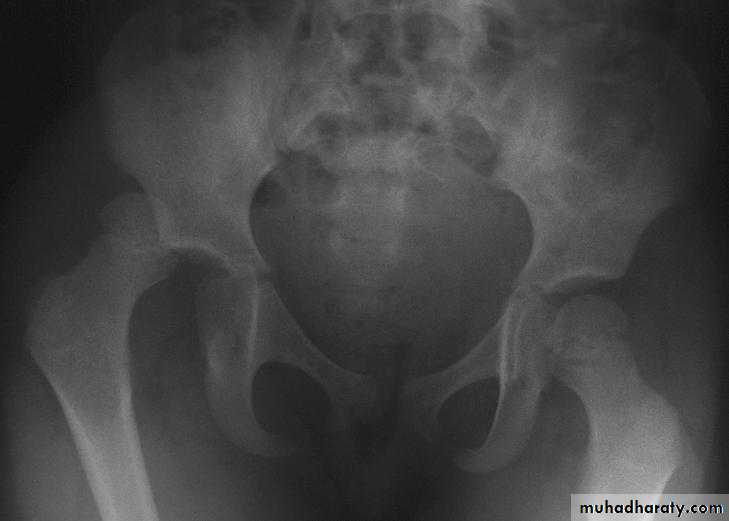

Inter-trochanteric fractures (extracapsular fracture)

.It is extra capsular fracture occurs in elderly..Unite quite easily and seldom cause a vascular necrosis.

Mechanism of injury:

Directly on trochanter.Twisting force indirectly.

The crack runs up between the lesser and greater trochanter.

Pathological anatomy divided into:

Stable:Unstable are those where

a. posteriomedial cortex is shattered.b. poor contact between fracture segment.

The leg is shorter and more externally rotated than intracapsular fracture.

Radiological examination

2 typesStable.

Unstable.